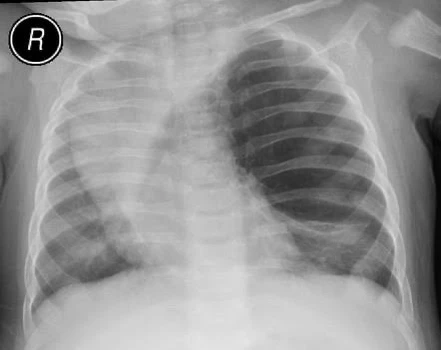

- Рентгенография органов грудной клетки — выявляется повышение прозрачности лёгочной ткани, смещение средостения в здоровую сторону, уплощение купола диафрагмы и расширение межрёберных промежутков на стороне поражения. Характерно поджатие здоровых отделов лёгкого в виде треугольной тени[4].